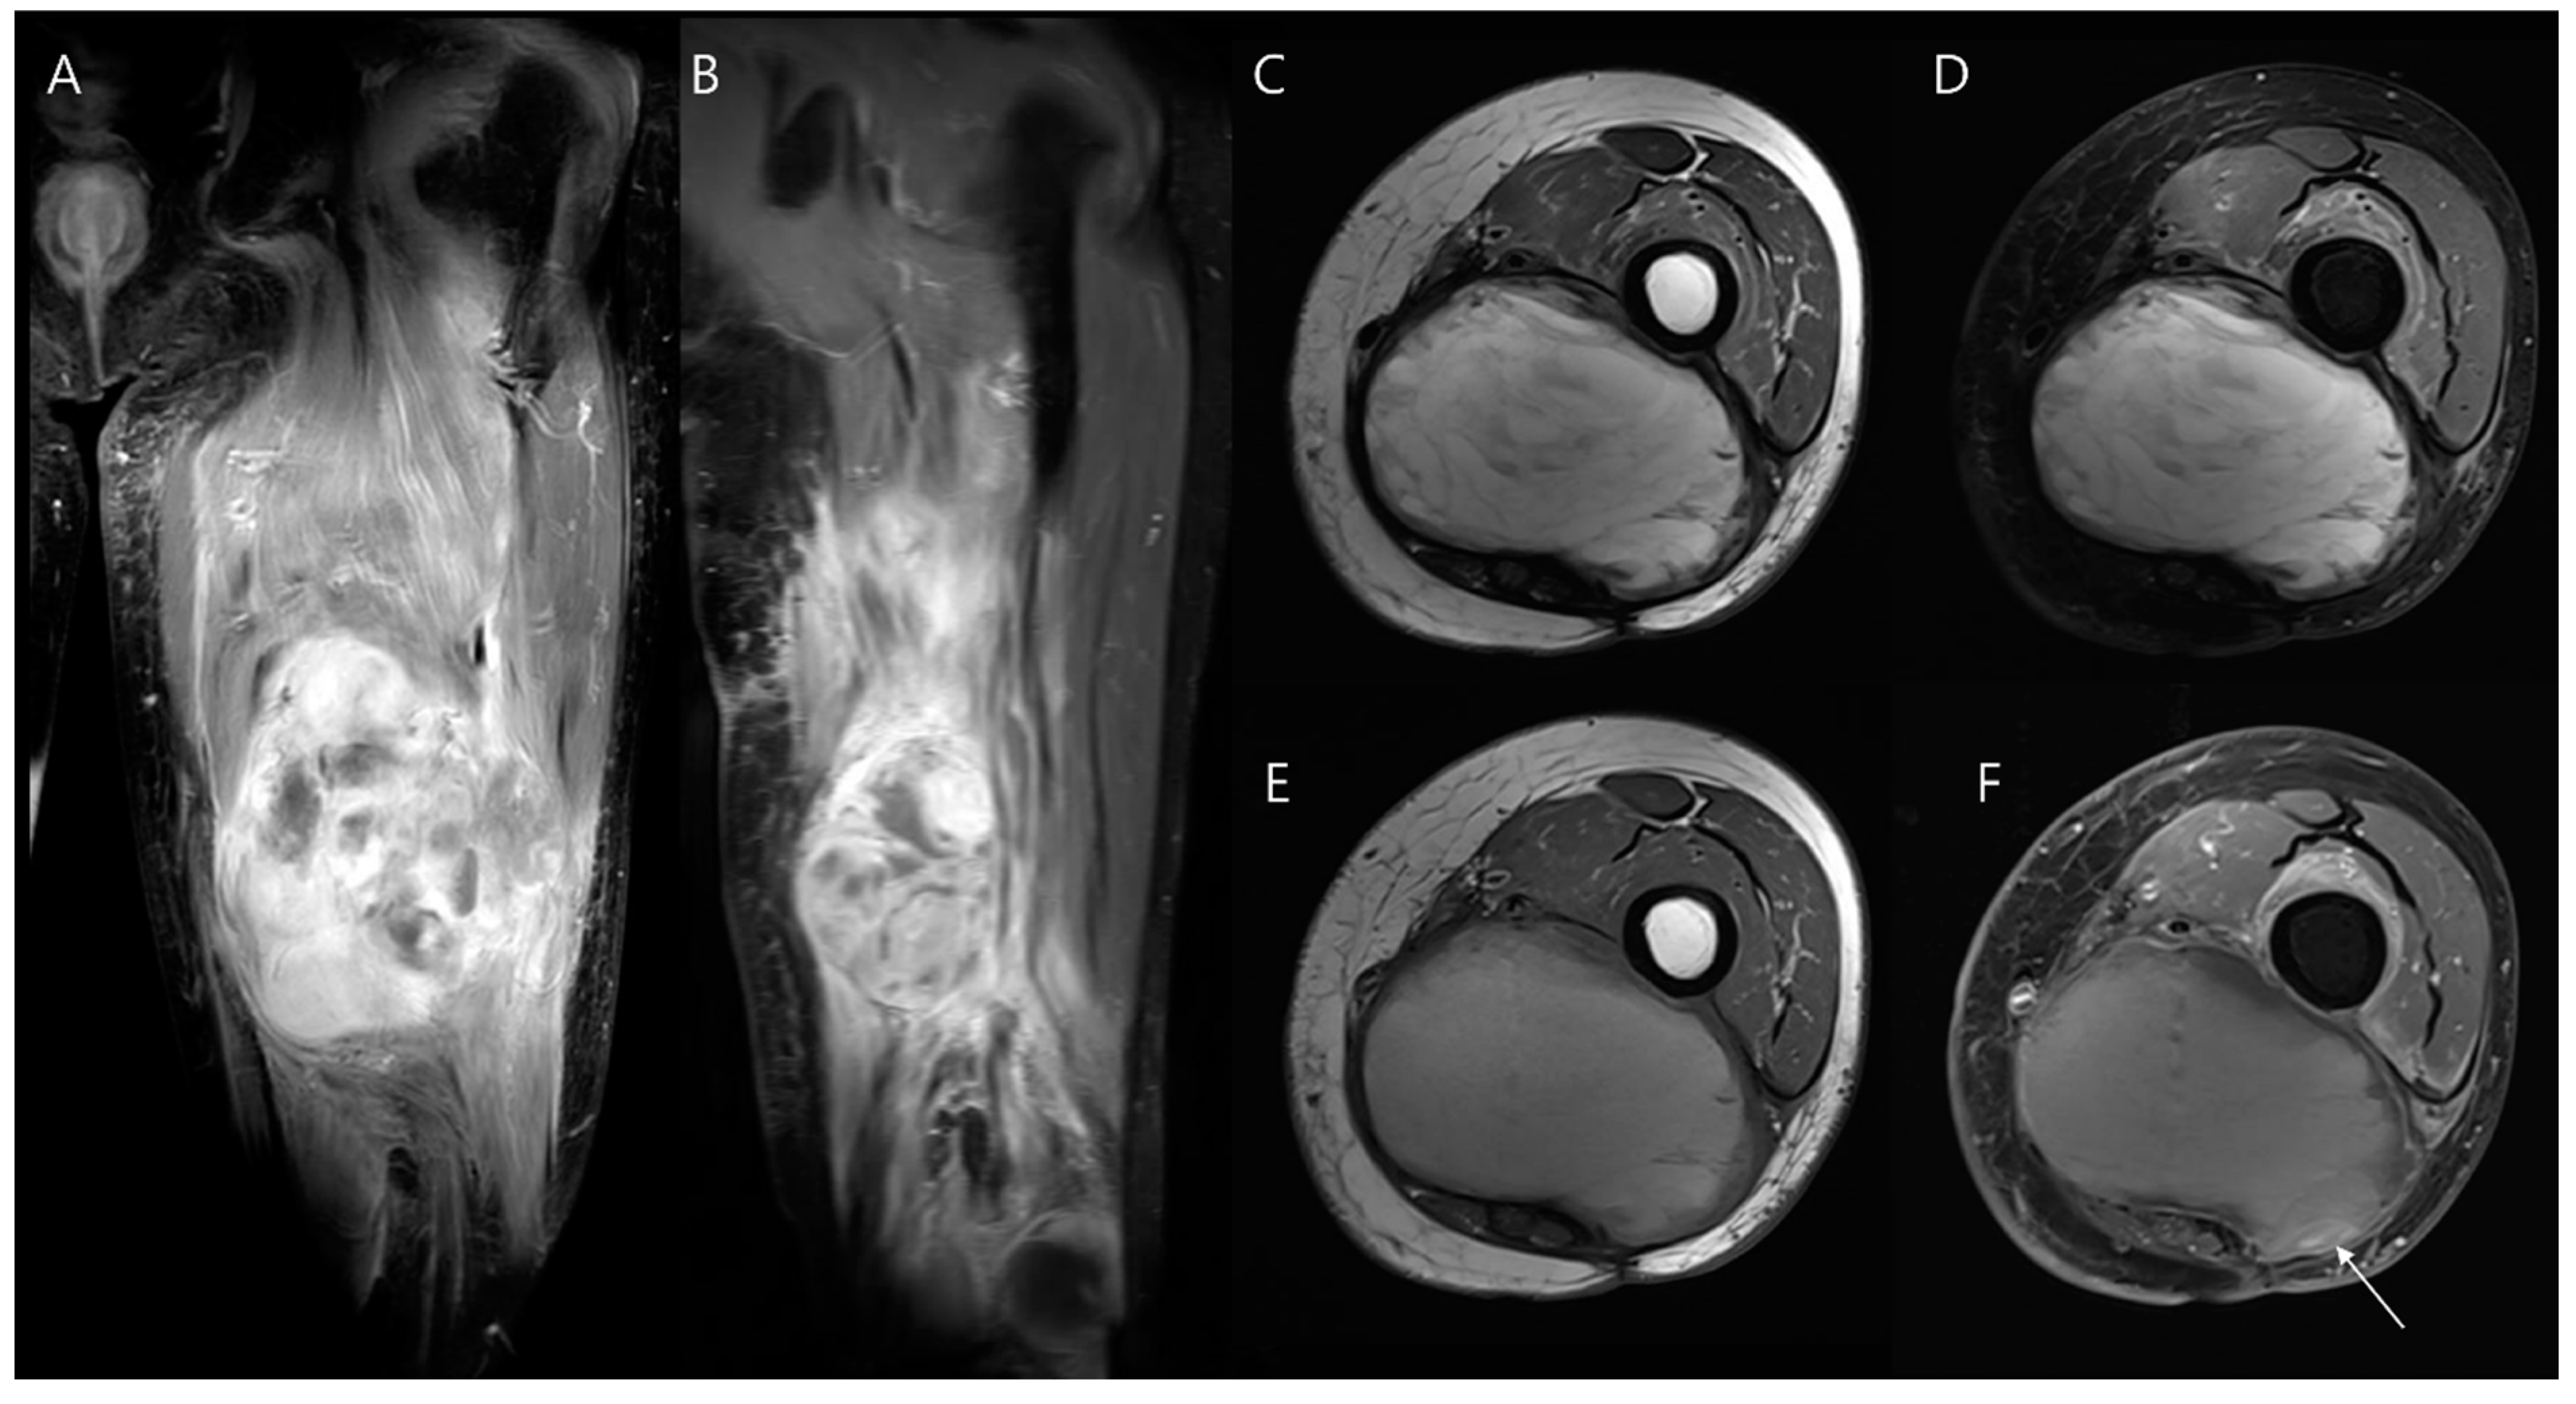

- Song, E.H.; Lee, S.Y.; Lee, S.; Jung, J.Y.; Shin, S.H.; Chung, Y.G.; Jung, C.K. Diagnosis of Local Recurrence of Malignant Soft Tissue Tumors after Reconstructive Surgery on MRI. J. Clin. Med. 2023, 12, 4369. [Google Scholar] [CrossRef]

- Kwee, R.M.; Kwee, T.C. Diagnostic performance of MRI in detecting locally recurrent soft tissue sarcoma: Systematic review and meta-analysis. Eur. Radiol. 2022, 32, 3915–3930. [Google Scholar] [CrossRef] [PubMed]

- Tavare, A.N.; Robinson, P.; Altoos, R.; LiMarzi, G.M.; Scherer, K.F.; Kransdorf, M.J.; Bancroft, L.W. Postoperative Imaging of Sarcomas. Am. J. Roentgenol. 2018, 211, 506–518. [Google Scholar] [CrossRef] [PubMed]

- Vibhakar, A.M.; Cassels, J.A.; Botchu, R.; Rennie, W.J.; Shah, A. Imaging update on soft tissue sarcoma. J. Clin. Orthop. Trauma 2021, 22, 101568. [Google Scholar] [CrossRef]

- Hirschmann, A.; van Praag, V.M.; Haas, R.L.; van de Sande, M.A.J.; Bloem, J.L. Can we use MRI to detect clinically silent recurrent soft-tissue sarcoma? Eur. Radiol. 2020, 30, 4724–4733. [Google Scholar] [CrossRef]